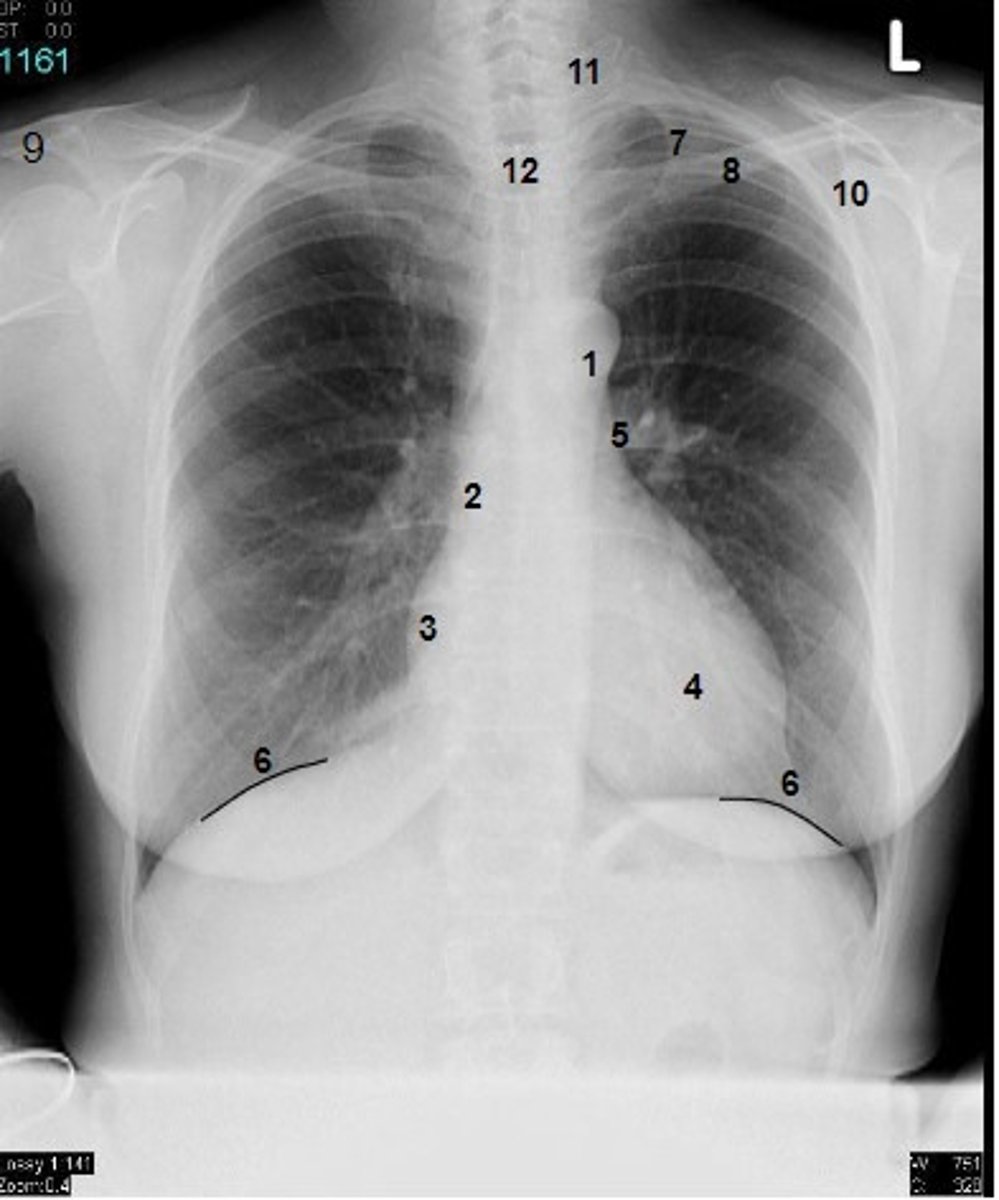

1

at what number is the arch of aorta?

2

at what number is the superior vena cava

3

at what number is the right atrium

4

at what number is the left ventricle

5

at what number is the primary bronchus

6

at what number is the dome of diaphragm

7

at what number is the first rib

8

at what number is the clavicle

9

at what number is the acromion of scapula

10

at what number is the coracoid process of scapula

11

at what number is the transverse process of vertebra

12

at what number is the spinous process of vertebra